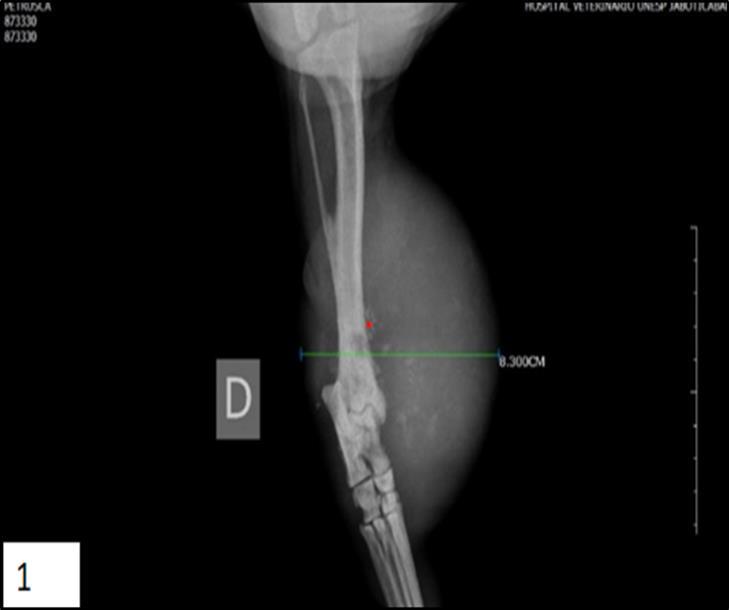

In dogs, there are no reports of radiographic studies with periosteal osteosarcoma. The information obtained in veterinary medicine comes from human medicine. Therefore, radiographic changes described in dogs were based on the changes described in humans Figure 1.

Figure 1.Lateral radiograph of an periosteal osteosarcoma involving the canine right tibia. The tumor displays an active periosteal reaction and homogeneous soft tissue mass adjacent on the distal third of tibia (*).